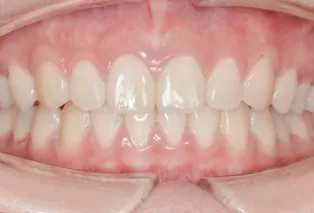

Intraoral photos

Intraoral photos after treatment